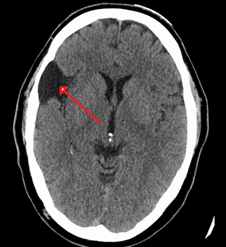

Medios de contraste

Se pueden apreciar imágenes que pueden confundirse con aneurismas o malformaciones vasculares, pero al detallarse en otro plano (coronal), las  identificamos como  variantes anatómicas como elongaciones, bifurcaciones ,  anomalías venosas del desarrollo o vasos tentoriales.

Fig. 11.